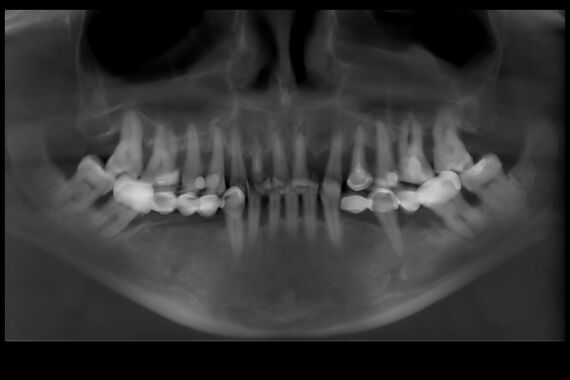

Пациентка обратилась с жалобами на неэстетичные металлокерамические коронки, которые уже менялись неоднократно, на подвижность зубов верхней и нижней челюсти.

Изучив данные 3D-исследования, которые пациентка прислала через интернет, доктор предложил провести протезирование верхней и нижней челюстей в кратчайшие сроки при помощи методики All-on-6 (все на 6-ти). Во время операции были удалены старые протезы, оставшиеся зубы, установлены 6 имплантатов на верхней и 6 имплантатов на нижних челюстях, и за 5 дней были изготовлены и фиксированы несъемные эстетичные протезы на обеих челюстях.